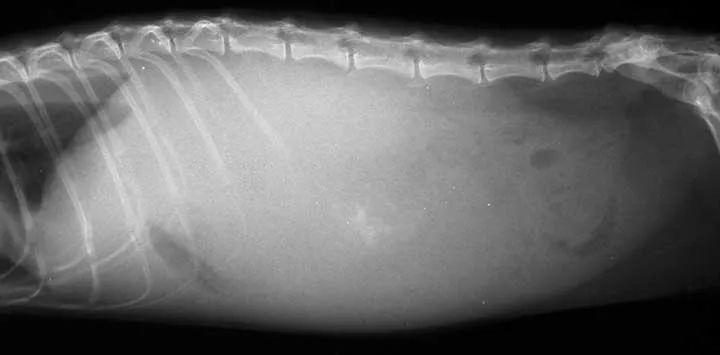

狗狗肚子突然出现围度增加,尤其是公狗,需要考虑腹水。如果是老年母犬,还需要关注子宫健康(子宫蓄脓也会出现腹围增大)。今天我们着重说一下狗狗腹水。

腹水指腹腔内蓄积非生理性液体(水和淋巴液),也称为腹腔积液,属于一种继发性疾病。幼年犬和老年犬容易出现,典型的表现为腹围增大、腰背凹陷。

比较有价值且性价比较高的检查包括:血常规、生化、尿检、X光片、超声(腹超、心超)、胰腺炎检测等,其他检查可以根据具体情况进行选择(腹水液体成分评估、胆汁酸检测、活检等)。